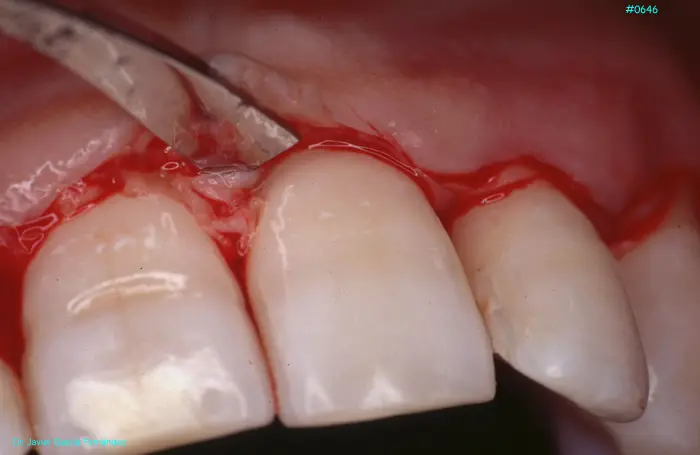

Atlas of Surgical Techniques in Periodontics. Chapter III. Atlas de Técnicas Quirúrgicas en Periodoncia